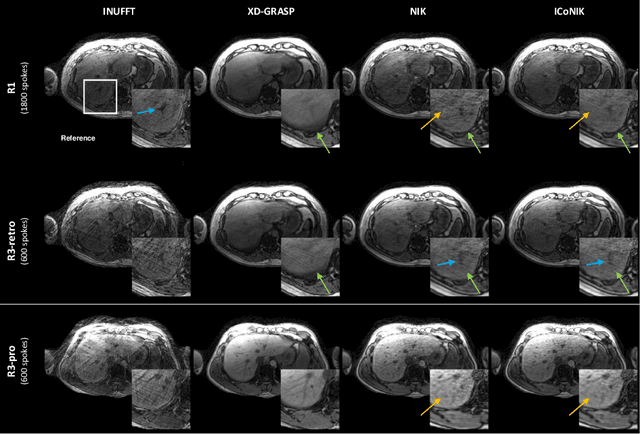

Abstract:Motion-resolved reconstruction for abdominal magnetic resonance imaging (MRI) remains a challenge due to the trade-off between residual motion blurring caused by discretized motion states and undersampling artefacts. In this work, we propose to generate blurring-free motion-resolved abdominal reconstructions by learning a neural implicit representation directly in k-space (NIK). Using measured sampling points and a data-derived respiratory navigator signal, we train a network to generate continuous signal values. To aid the regularization of sparsely sampled regions, we introduce an additional informed correction layer (ICo), which leverages information from neighboring regions to correct NIK's prediction. Our proposed generative reconstruction methods, NIK and ICoNIK, outperform standard motion-resolved reconstruction techniques and provide a promising solution to address motion artefacts in abdominal MRI.